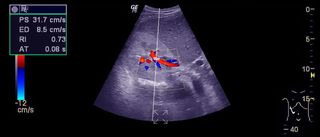

Ecografia cardiacă Doppler este o formă avansată de ecocardiografie care folosește ultrasunete pentru a crea imagini ale inimii în mișcare și pentru a evalua fluxul sanguin. Componenta Doppler măsoară direcția și viteza cu care sângele circulă prin inimă și vasele mari, oferind informații esențiale despre funcționarea normală sau patologică a sistemului cardiovascular. Practic, nu doar vezi inima, ci „vezi” și cum curge sângele prin ea.

În cadrul ecografiei cardiace pot fi utilizate mai multe tipuri de Doppler. Dopplerul color arată fluxul sanguin sub formă de culori, evidențiind eventualele refluxuri sau turbulențe. Dopplerul pulsat și continuu măsoară viteza exactă a sângelui și ajută la evaluarea severității unor afecțiuni, precum stenozele sau insuficiențele valvulare. Aceste tehnici se completează reciproc pentru un diagnostic cât mai precis.